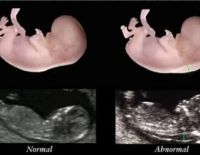

Đo độ mờ da gáy là gì và ý nghĩa khi thực hiện trong thai kỳ

Một trong những kiểm tra cần thiết trong thai kỳ mẹ cần thực hiện là đo độ mờ da gáy. Việc đánh giá thai nhi có nguy cơ bị bệnh Down hay không chính là nhờ vào phương pháp này. Tuy nhiên, tính chính xác...